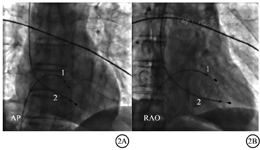

患者麻醉及外科手术过程顺利,术后重症监护病房(ICU),心电图示窦性心律、LBBB,心率65次/min(图1A)。术后第2天转入普通病房,8 h后,心电监测示患者心率突降至30次/min,可见起搏间歇性失夺获和长间歇心脏停搏,血压80/50 mmHg(1 mmHg=0.133 kPa)。起搏测定示起搏阈值升至8.0 V,调整起搏输出电压10.0 V,起搏频率100次/min,患者血压及心率得到一定程度的稳定。急查血电解质、心肌酶谱均正常,床边超声心动图检查排除心包积液和心脏压塞。患者再次进入导管室拟行冠状动脉造影及再次置入临时起搏电极。X线透视示临时起搏电极导线从右心室心尖部移位至右心室间隔部近端,解剖学上右束支分布的区域(图2)。冠状动脉造影示病变同上次结果,未发现急性心肌缺血证据。据此推断,因临时起搏电极脱位,机械损伤右束支致右束支传导阻滞,在已存在LBBB的基础上导致完全性(三度)房室传导阻滞。另一根6 F双极起搏电极导线(401770型双极临时起搏电极导线,美国雅培公司)经右侧颈内静脉置入右心室心尖部(图2)。测定起搏参数示起搏阈值0.9 V,设定临时起搏输出频率80次/min,输出电压6.0 V。

注:1=移位至室间隔的起搏电极导线(经右股静脉首次植入);2=到位于心尖部的起搏电极导线(经右颈内静脉再次植入);AP=前后位;RAO=右前斜位